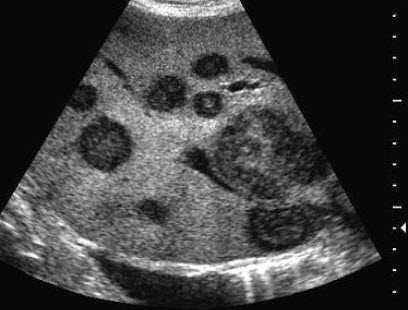

11、单项选择题

某患者阴囊增大,自诉用力时阴囊可增大,平卧缩小,无外伤史。B超检查超声声像图如下,最可能的诊断为()

A.鞘膜积液

B.附睾炎性包块

C.斜疝

D.附睾结核

E.股疝